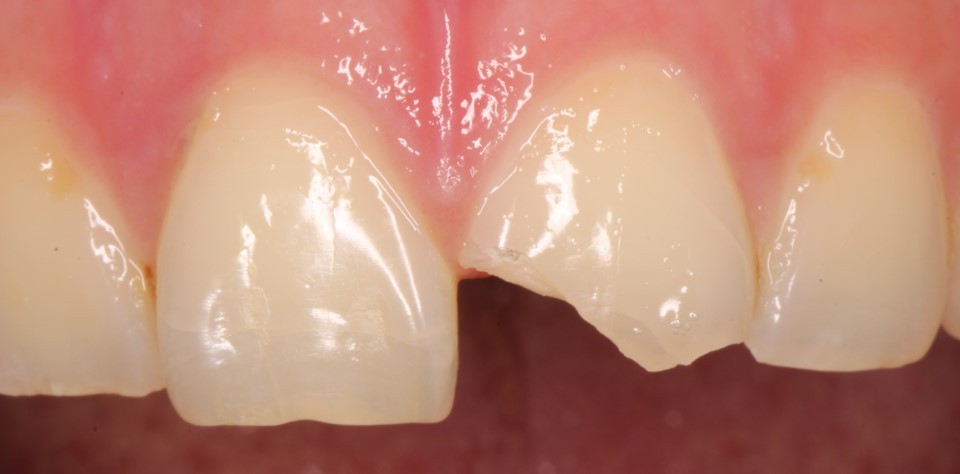

Внутриротовые фотографии 17.10.2022г

На данной фотографии продемонстрирована припасовка осколка зуба. Далее зуб и осколок был вычищен и адгезивно подготовлен к фиксации.